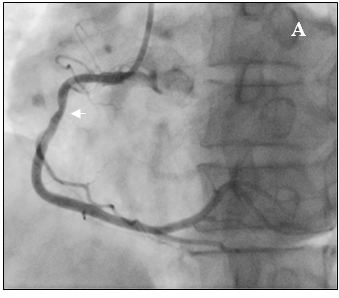

Tại cấp cứu bệnh nhân được chẩn đoán nhồi máu cơ tim cấp vùng hoành giờ thứ 2, block A-V độ 3, có chỉ định chụp mạch vành cấp cứu. Kết quả chụp mạch vành cho thấy hẹp nặng lan tỏa nhiều đoạn ở cả động mạch vành trái (hình 2a) và động mạch vành phải (hình 2b).

Hình 2b: Hệ mạch vành ưu thế phải, hẹp lan tỏa RCA

Tại phòng thông tim huyết áp bệnh nhân thấp 80/60mmHg nên chúng tôi không dùng Nitroglycerin. Sau khi chụp thấy hẹp nặng lan tỏa ở cả ba nhánh của động mạch vành, không loại trừ do co thắt nên chúng tôi đã tiến hành bơm 500µg Nitroglycerin vào động mạch vành. Kết quả chụp lại hiện tượng trên hoàn toàn biến mất, động mạch vành phải và trái thâm nhiễm nhẹ nhưng đều có kích thước lớn hơn nhiều so với ban đầu, dòng chảy TIMI 3 (hình 3a-3b), đồng thời huyết áp của bệnh nhân cũng cải thiện rõ 120/80 mmHg.